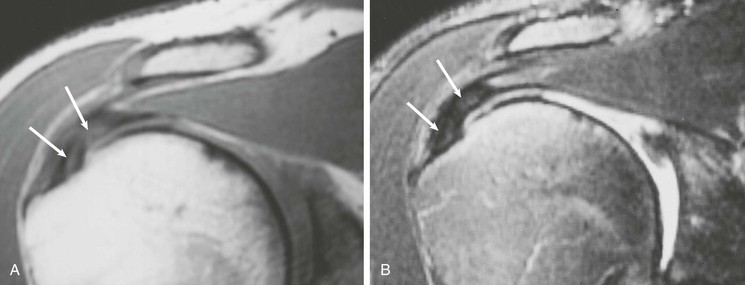

Partial-thickness tears (Figs. 44-18, 44-19, and 44-20) can occur on either the articular surface or the bursal surface or within the substance of the tendon. Articular surface tears are the most common type to occur (see Fig. 44-18). A partial-thickness tear is seen on MRI as an area of increased signal on T1-weighted images that increases to fluid signal intensity on T2-weighted images. The fluid signal intensity extends only partially through the thickness of the tendon from superior to inferior. These tears may partially heal with granulation tissue, making them difficult to distinguish from tendinopathy on MRI. MRA is more sensitive than conventional MRI in detecting articular surface tears; however, it does not increase sensitivity for detecting partial-thickness tears of the bursal surface. It has been suggested that the sensitivity for detecting partial-thickness undersurface tears can be further improved by adding the ABER view to the MRA protocol.55,104,105

Interstitial tears of the rotator cuff represent tears that occur within the substance of the tendon but do not involve the bursal or the articular surface (Fig. 44-19). These tears are demonstrated on MRI as a focal linear area of fluid signal that is contained within the substance of the tendon, and they typically occur at the footprint of the supraspinatus tendon as it attaches to the greater tuberosity of the humeral head.

A partial articular-sided supraspinatus tendon avulsion lesion is a subset of partial-thickness tears.106,107 The tear represents a partial-thickness articular-sided avulsion of the supraspinatus tendon at its most anterior attachment site. This type of tear deserves special attention and should be accurately described on MRI because the recommended treatment for this subset of tendon tears differs from the standard partial-thickness tears described previously. On MRI, a small articular-sided avulsion is seen as fluid signal extending into the articular surface of the supraspinatus tendon at its anterior attachment site with partial avulsion of the tendon at this level, and this lesion represents a subset of the articular surface partial-thickness tears (Fig. 44-20).